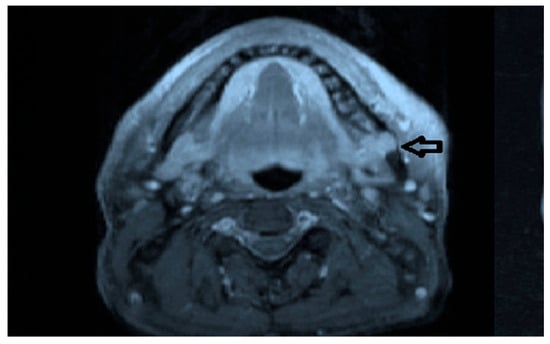

Intraoral examination revealed an exophytic erythematous lesion measuring approximately 2.5 × 2 cm on the left retromolar trigone, while orthopantomographic X-ray imaging demonstrated a corresponding radiolucency in the same region (Figure 2). Considering her systemic condition and ongoing therapy with cyclophosphamide, a multidisciplinary management plan was initiated, which included second-level imaging (MRI) to evaluate lesion extension (Figure 3), a professional oral hygiene session, chlorhexidine 0.12% mouth rinses, and selective grinding of the occlusal cusps of the involved mandibular molars to minimize traumatic contact. An incisional biopsy was then performed using a cold scalpel combined with CO2 laser, along with extraction of tooth 3.8, suspected to contribute to local trauma. Histopathological evaluation of this specimen revealed only epithelial alterations and abundant granulation tissue without evidence of neoplasia, and a definitive diagnosis could not be established at this stage (Figure 4a,b).

Figure 2.

OPG x-ray and the blue arrow show a focus of radiolucency behind the lower-left third molar.

Figure 3.

MRI view of the left retromolar region showing with the indication of black arrow a soft-tissue lesion corresponding to the clinical site of the Kaposiform hemangioendothelioma.